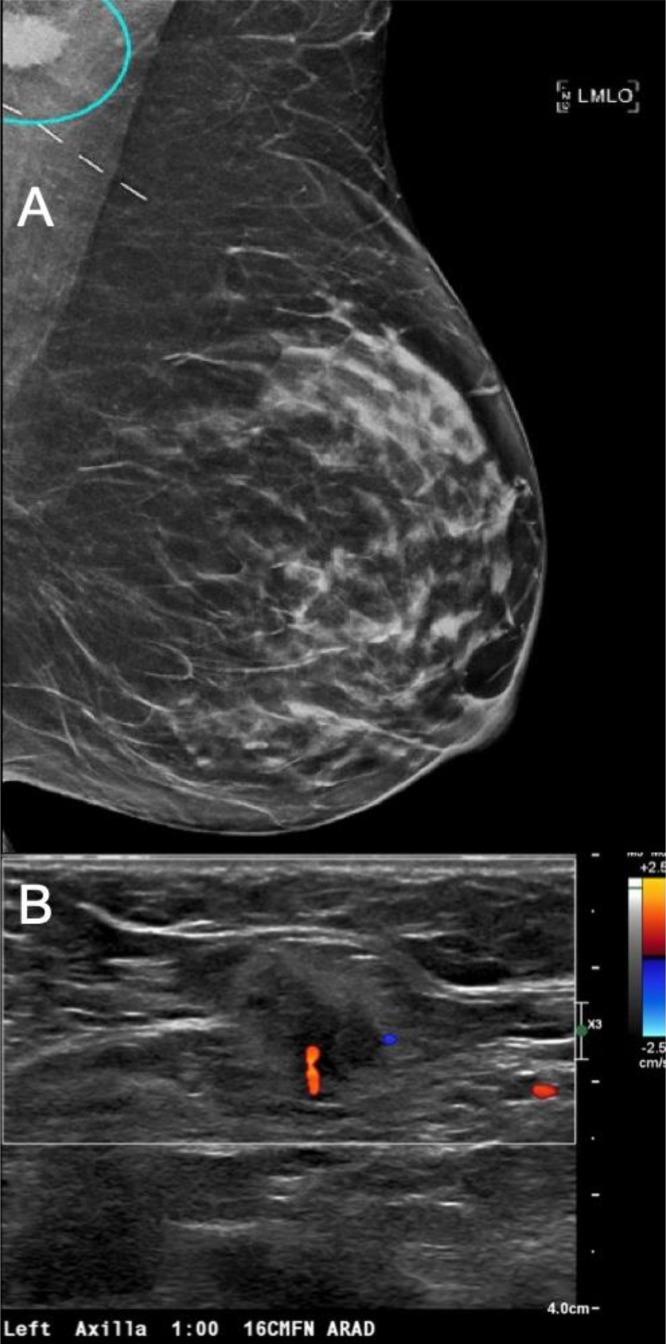

Basal cell carcinoma (BCC) is the most common nonmelanoma skin cancer but rarely metastasizes, with an estimated metastatic rate of 0.1%. Metastatic spread to axillary lymph nodes is extremely uncommon, and to our knowledge, no prior cases have reported incidental detection on screening mammography. We report the case of a 48-year-old Caucasian female with a history of renal transplants, chronic immunosuppression, and multiple biopsy-confirmed BCCs and cutaneous squamous cell carcinomas who presented with a new axillary mass incidentally found on screening mammography. Final pathology following axillary lymph node dissection revealed metastatic BCC. This case illustrates the diagnostic complexity of axillary masses found on screening mammography and underscores the need for vigilant evaluation of BCC metastases in immunosuppressed patients. It highlights the diagnostic limitations of imaging and core biopsy in distinguishing BCC from cutaneous squamous cell carcinomas or metastatic breast carcinoma. Given the poor prognosis of metastatic BCC, this report supports more proactive imaging strategies in high-risk individuals and emphasizes the need for further research into optimal management.

基底细胞癌(BCC)是最常见的非黑色素瘤皮肤癌,但很少发生转移,估计转移率为0.1%。转移至腋窝淋巴结极为罕见,据我们所知,此前尚无在乳腺钼靶筛查时偶然发现转移的病例报道。我们报告一例48岁的白种女性,有肾移植、慢性免疫抑制病史,且经多次活检确诊患有基底细胞癌和皮肤鳞状细胞癌,其在乳腺钼靶筛查时偶然发现腋窝有一新肿块。腋窝淋巴结清扫术后的最终病理显示为转移性基底细胞癌。该病例说明了乳腺钼靶筛查时发现腋窝肿块的诊断复杂性,并强调了对免疫抑制患者基底细胞癌转移进行警惕性评估的必要性。它突出了影像学检查和粗针活检在区分基底细胞癌与皮肤鳞状细胞癌或转移性乳腺癌方面的诊断局限性。鉴于转移性基底细胞癌预后较差,本报告支持对高危个体采取更积极的影像学策略,并强调需要进一步研究最佳治疗方案。